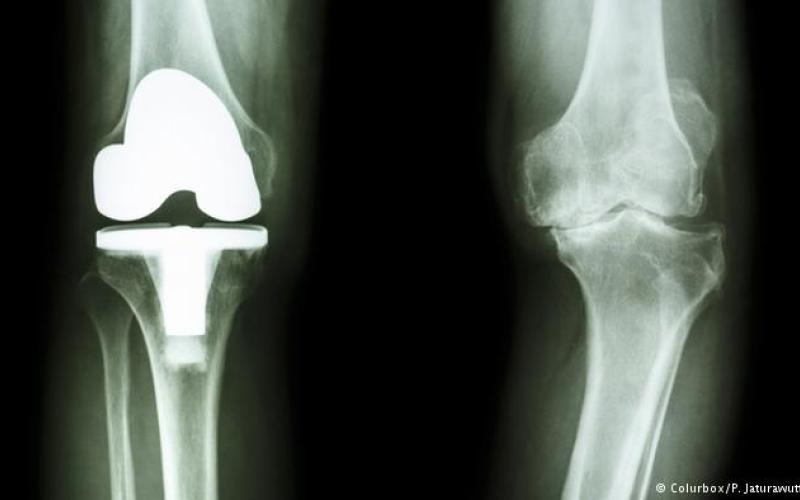

عمل جراحی تنها زمانی توصیه می‌شود که هیچ یک از روش‌های محتاطانه موثر نباشد. پیوند غضروف، پروتز و آرتروسکوپی از روش‌های موجود برای درمان به‌وسیله اعمال جراحی است. تشخیص بهترین روش درمان فقط در صلاحیت پزشک متخصص است.